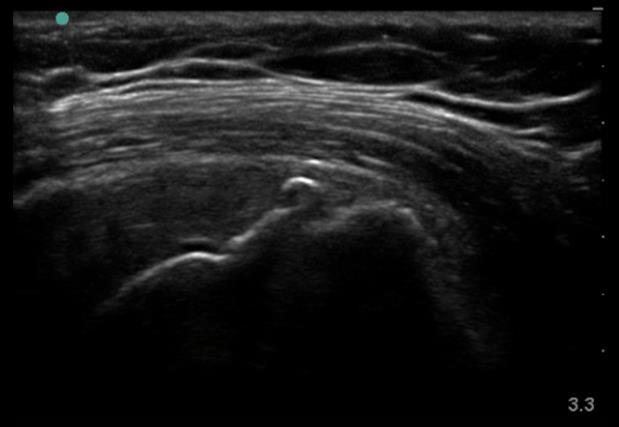

上腕首の肩骨棘画像